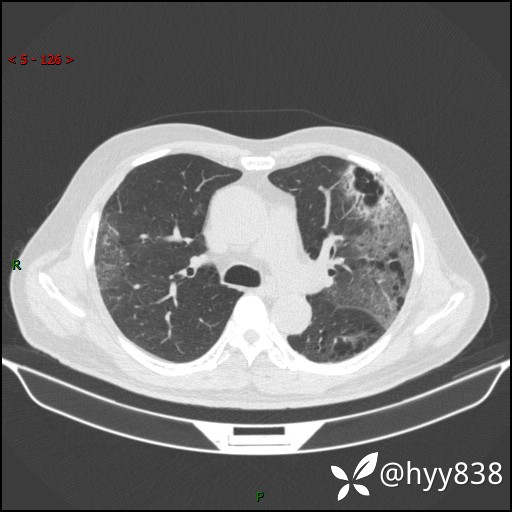

一周前胸部CT